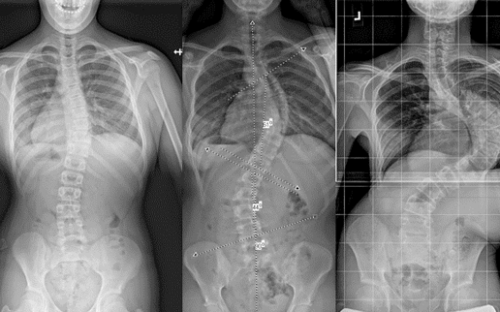

يُعد الحزام الطبي أحد أكثر الطرق فعالية لعلاج اعوجاج العمود الفقري عند المراهقين ومنع تفاقم الانحناء خلال مرحلة النمو. ومع اقتراب انتهاء فترة العلاج، يتساءل الكثير من الأهل: ماذا يحدث بعد إزالة الحزام؟ هل سيعود الانحناء؟ وكيف يمكن متابعة الحالة والحفاظ على النتائج؟ هذا المقال يقدّم إجابات مفصلة بطريقة سهلة الفهم للأهل، مع التركيز على الوقاية والمتابعة بعد التوقف عن الحزام.

تشير الدراسات إلى أنّ الانحناء قد يعود بعد إزالة الحزام، لكنه عادةً يمر بعدة مراحل:

بعد إزالة الحزام مباشرة، قد تُسجَّل زيادة متوسطة في زاوية كوبب بمعدل درجات بسيطه. هذا أمر طبيعي ويُعتبر جزءًا من استجابة الجسم للتوقف عن الدعم الخارجي.المرحلة قصيرة الأمد (حتى 5 سنوات):

خلال هذه الفترة، قد يزداد الانحناء بمعدل تقريبي 0.8 درجة سنويًا، لذلك يُنصح بالمتابعة الدقيقة مع الطبيب لملاحظة أي تغيّر في زاوية الانحناء أو شكل الظهر.المرحلة الطويلة الأمد (بعد 5 سنوات):

يقل معدل تفاقم الانحناء تدريجيًا ليصل إلى حوالي 0.2 درجة سنويًا، خاصة إذا كان المراهق ملتزمًا بالتمارين الموصوفة والمتابعة الطبية الدورية.

نجاح الحزام الطبي لعلاج اعوجاج العمود الفقري عند المراهقين لا يعتمد على ارتدائه فقط، بل على تفاصيل دقيقة مثل تصحيح دوران الفقرات الأولى وسرعة هذا التصحيح. متابعة الأهل مع الطبيب، الالتزام بعدد ساعات الارتداء، واستخدام الحزام المصمم خصيصًا لكل طفل، جميعها عوامل تزيد من فعالية العلاج وتمنح الطفل فرصة أفضل لنمو ظهر مستقيم وحياة طبيعية.

التطور الكبير في تصميم الأحزمة الطبية جعل علاج اعوجاج العمود الفقري عند المراهقين أكثر نجاحًا وأقل إزعاجًا. باستخدام تقنيات التصوير الثلاثي الأبعاد والمحاكاة الرقمية، أصبح الحزام أكثر خفة وراحة، ويعطي نتائج أفضل في تصحيح الانحناء والتواء العمود الفقري.